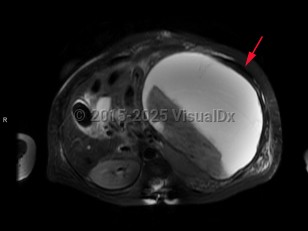

Splenic infarction

A splenic infarction is an ischemic injury to the spleen. It most commonly presents with severe, sharp pain, with a quarter of patients presenting with classic left upper quadrant pain and about half with pain elsewhere in the abdomen; a significant portion have no abdominal pain. Radiation to the left shoulder may sometimes occur, called a Kehr sign. Leukocytosis and fever may also be present. Infarction may lead to rupture, which can cause life-threatening hemorrhage.

Splenic infarction